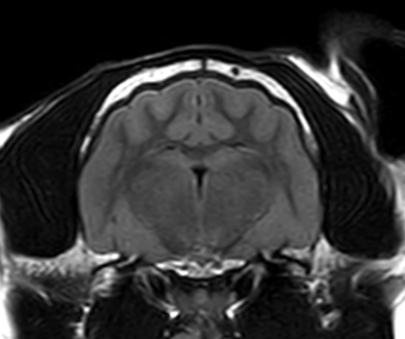

3T MRI

기존 본원에서 이용하던 1.5T 장비와 비교하여 높은 해상도와 빠른 스캔 시간(촬영 부위 당 30분 미만)으로 MR 촬영 시 환자의 마취 부담을 줄일 수 있습니다.

3T MRI는 국내 동물병원에서 최상급 촬영 장비에 해당하며 본동물의료센터의 MRI는 3T MRI 중에서도 하이엔드급 장비(Philips Ingenia)를 사용하고 있습니다.

TRANS, T2WI

TRANS, FLAIR

TRANS, T1WI IR

두개 내 출혈(개)

소뇌 경색(개)

뇌 수두증(고양이)

01뇌 MRI

· 뇌신경계 질환의 정확한 감별 및 조기진단

· 뇌수두증, 뇌출혈, 뇌종양, 뇌수막염, 소뇌탈출 등

· 전정계(중이, 내이) 질환의 진단

· 안구질환의 진단